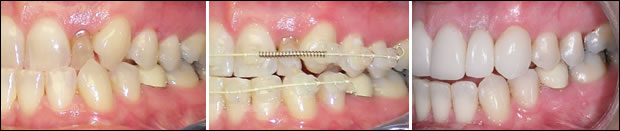

Fig 8: Site #10; the retained deciduous tooth, space being provided, the restored dental implant respectively.